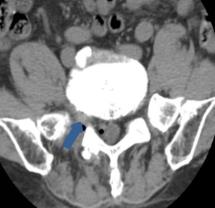

• 单纯内镜乳头小球囊扩张术在胆总管较大结石中的应用效果及安全性

2025, 31(12):56-63. DOI: 10.12235/E20250208

摘要 (70) HTML (39) PDF 743.90 K (64) 评论 (0) 收藏

摘要:目的 分析内镜乳头小球囊扩张术(EPSBD)治疗胆总管较大结石(直径10~15 mm)的临床效果及安全性。方法 选择2020年1月-2023年12月该院收治的胆总管较大结石(直径10~15 mm)患者142例,采用随机数表法分为观察组与对照组,各71例。观察组行EPSBD(扩张球囊直径10 mm)治疗,对照组行内镜十二指肠乳头括约肌切开术(EST)联合球囊扩张术(EPBD)治疗。比较两组患者围手术期相关指标(取石成功率、取石时间、术后首次排便时间和住院时间),术前和术后48 h肝功能指标[总胆红素(TBiL)、谷丙转氨酶(GPT)和谷草转氨酶(GOT)],术后早期与远期并发症的发生情况,以及术后12个月内实施腹腔镜胆囊切除术(LC)情况。结果 两组患者取石成功率、取石时间、术后首次排便时间和住院时间比较,差异均无统计学意义(P > 0.05);术后48 h,两组患者血清TBiL、GPT和GOT水平明显低于术前,差异均有统计学意义(P < 0.05),但两组间比较,差异均无统计学意义(P > 0.05);观察组术后早期并发症发生率为11.27%,与对照组的8.45%比较,差异无统计学意义(P > 0.05);观察组术后远期并发症发生率为2.82%,明显低于对照组的16.90%,差异有统计学意义(P < 0.05);术后12个月内,观察组有5例实施了LC,对照组有4例实施了LC,两组间比较,差异无统计学意义(P > 0.05)。结论 应用EPSBD治疗胆总管较大结石(10~15 mm),与EST + EPBD治疗方案相比,能获得相近的取石成功率,但前者有利于降低远期并发症的发生率。值得临床推广应用。